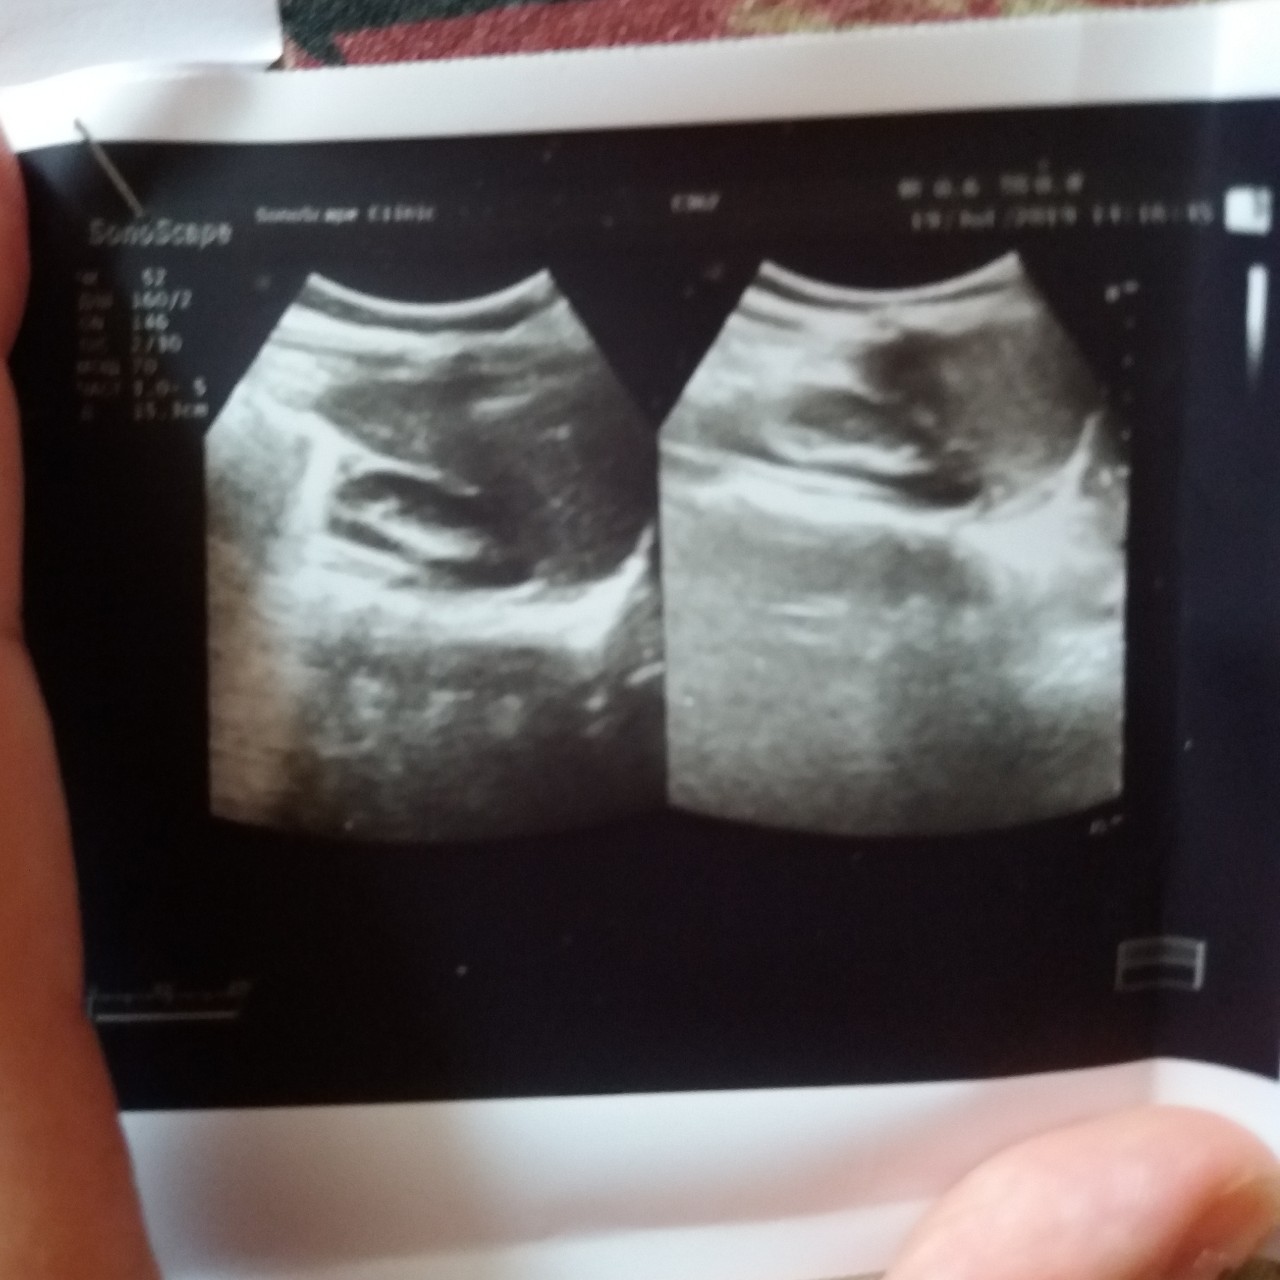

Добрый день. Хочу обратиться к Вам в продолжении нашей проблемы. Вы порекомендовали сдать бак посев мочи, мы ждем направление. А пока сдали по ничпоренко и узи почек и мочевого. Сегодня у ребенка моча мутная весь день. Вот результаты. Канефрон еще пить не начинали. Подскажите пожалуйста по данным апализам что можете сказать. Заранее спасибо.